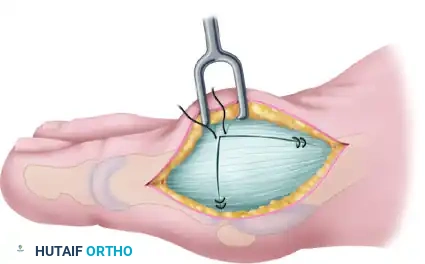

Step 3: The Inverted-L Capsulotomy

To maximize the effectiveness of the revision capsular imbrication, an extensive dorsal exposure is required. Commonly, a thin slip of accessory extensor tendon is visible; this serves as a helpful anatomical landmark. If absent, locate the dorsal and medial juncture of the rounded distal first metatarsal head.

Using either the medial aspect of the accessory tendon or the dorsomedial border of the first metatarsal as a starting point, perform an inverted-L capsulotomy. Complete a capsular-periosteal excision from the first MTP joint line extending proximally to the junction of the middle and distal thirds of the metatarsal.

Begin the transverse limb of this incision exactly at the joint line. Applying axial traction on the hallux helps to identify the distal edge of the metatarsal head, preventing inadvertent scoring of the articular cartilage with the scalpel. The transverse limb extends from dorsal to plantar through the capsule and the conjoined capsular-abductor hallucis tendon insertion, terminating 2 to 3 mm medial to the tibial sesamoid.

Step 4: Capsular Flap Elevation

With a small, pointed blade (e.g., a #15 blade), carefully raise the medial capsule from the underlying bone. Begin at